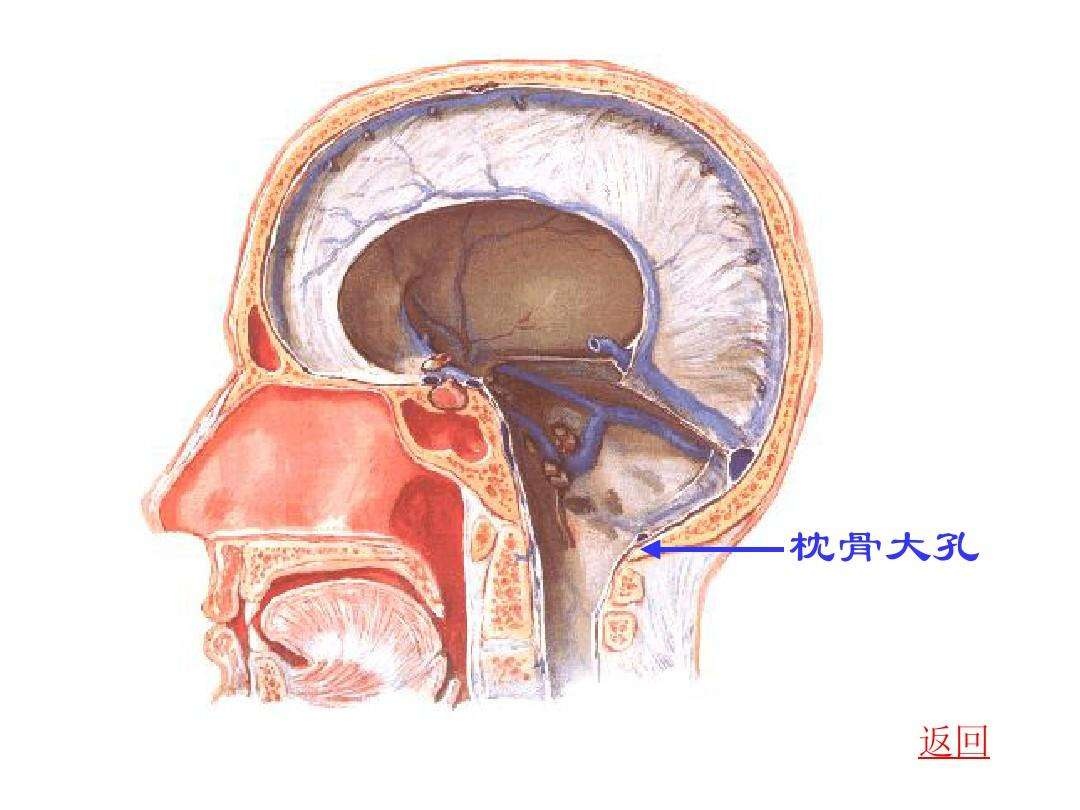

系统解剖实验的幻灯片 枕骨大孔

当小脑扁桃体向下疝出超过枕骨大孔下缘5mm即可诊断为小脑扁桃体下疝

颅内疝包括:大脑镰下疝,中心疝,海马钩回疝,小脑扁桃体下疝.